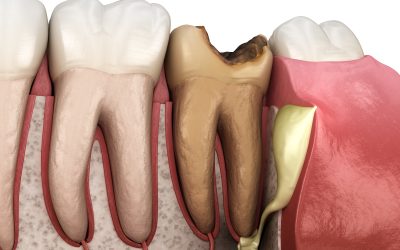

Ascesso dentale: cosa sono l’apicale e il parodontale

Esistono diverse tipologie di ascesso dentale, tra cui i più comuni sono l’ascesso apicale e quello parodontale. Il primo si forma all’estremità della radice del dente ed è spesso causato da una carie, mentre il secondo interessa la gengiva vicino alla radice ed è legato a un’infezione parodontale.